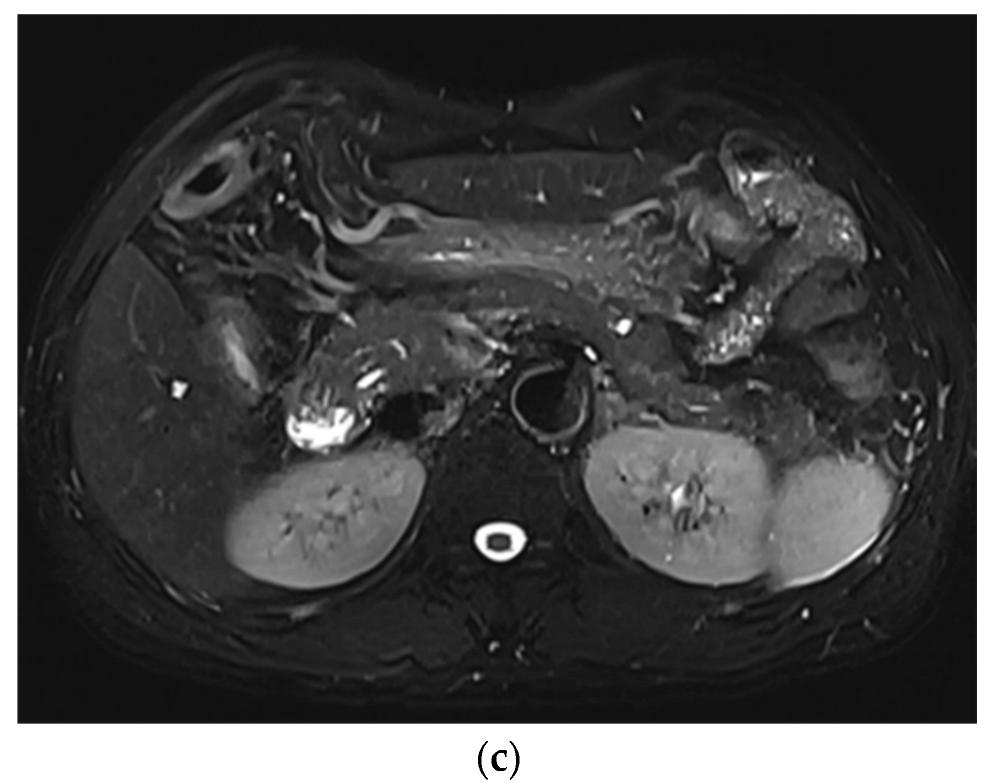

3. Results

3.1. Subjective Image Quality

3.2. Lesion Assessment